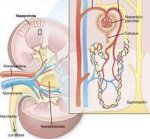

Диагностированный рак почки - это еще не приговор. Даже с таким, казалось бы, непобедимым диагнозом можно и нужно бороться. Карцинома почки является медленно растущей опухолью с медленным метастазированием, поэтому хирургический способ лечения этого заболевания дает полное излечение в 93% случаев. Хирургическое лечение рака почки в Израиле - наилучший способ борьбы. Вот примерный план действий